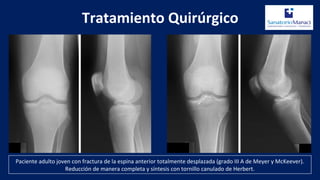

Paciente adulto joven con fractura de la espina anterior totalmente desplazada (grado III A de Meyer y McKeever).

Reducción de manera completa y síntesis con tornillo canulado de Herbert.